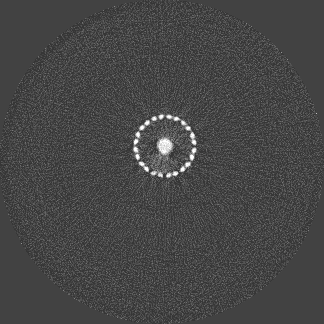

Photon-counting detectors have been successfully employed in preclinical applications. Using spectral imaging, a novel approach towards minimising beam hardening effects is proposed. To the best of our knowledge, beam hardening and metal artefact reduction using spectral imaging has not been reported. Unlike numerical techniques, the work described in this paper aims at minimising metal artefacts in the acquisition stage, by capturing high energy quanta that exhibit less beam hardening effects. The Medipix ASIC allows simultaneous data acquisition from discrete user-defined energy ranges. The ASIC was designed to count photon events and categorise them based on energy thresholds determined by the user. This feature enables the capture of spectral signatures for multiple materials which can be used for material discrimination. The number of counts for discrete energy bands can be obtained by subtracting data from two counters. This is essentially done as a pre-processing step prior to flat-field normalization and reconstruction. The raw data from a counter has an energy range between [, kVp], where is the corresponding user-defined threshold and kVp is the x-ray tube potential used. Since the count information is acquired simultaneously in a single exposure, the noise in a particular energy range is local Poisson noise due to quantum fluctuations. Reduction in streak artefacts using spectral imaging of a scaffold sample is shown in figure 1. Wide energy acquisition shows severe streaks while narrow high energy range exhibits reduced artefacts. Also, spatial improvements corresponding to the metal region can be noticed in the narrow energy band while the wide energy reconstruction shows a blooming effect.

Figure 3 shows a single slice spectral reconstruction of the Ti phantom. The cupping effect is prominent in the low energy range and decreases in the high energy acquisitions. The thresholds were determined to provide a trade-off between reduced photon noise and cupping effect. The spectral images for the energy ranges 55 to 80 keV and 62 to 80 keV exhibit reduced cupping effect while the 15 to 80 keV reconstruction has low quantum noise and shows good contrast in non-metal regions. In figure 4, a horizontal line profile passing through the origin of the metal cylinder shows cupping effect in the different energy ranges. Without the use of any hardware filters, a significant reduction in the cupping effect is noticeable in figure 4c. The reconstruction corresponding to the energy range from 62 to 80 keV suffers from severe photon limitation giving rise to statistical noise. Any significant increase in tube current and/or exposure time for this scan resulted in detector saturation in non-metal regions.

Figure 5 illustrates a single slice spectral reconstruction of the Ti scaffold. Varying levels of streak artefacts can be seen across the spectral reconstructions. The spectral reconstructions for the energy ranges 35 to 80 keV, 55 to 80 keV, and 62 to 80 keV shown in figure 5, exhibit reduced streak artefacts. A region-of-interest (ROI) analysis was performed in the immediate vicinity of the metal region where the streaks are more pronounced. Average attenuation coefficent of air close to zero conveys less regional noise/artefacts. The regional average attenuation coefficient () of the non-metal (air) region in 55 to 80 keV reconstruction (figure 5c) shows reduced artefacts. Even though minor streaks and statistical noise appear in figure 5d due to photon limitation, the artefacts are less pronounced in comparison to the wide energy acquisition in figure 5a.